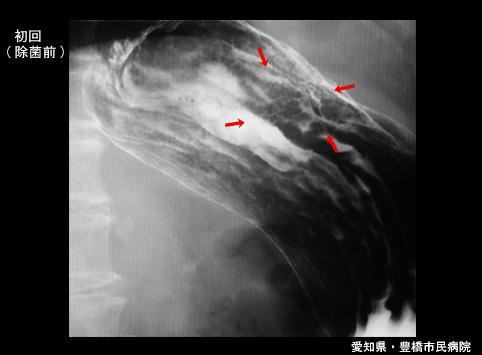

A case of gastric MALT lymphoma in which radiation therapy was effective.

Aichi Pref., 豊橋市民病院 (豊橋市民病院, Dr. 後藤)

Malignant Lymphoma/Malignant lymphoma

Stomach/Body

X-ray

Type 0/IIa (IIa+IIc) Superficial elevated and depressed type

25 - 29